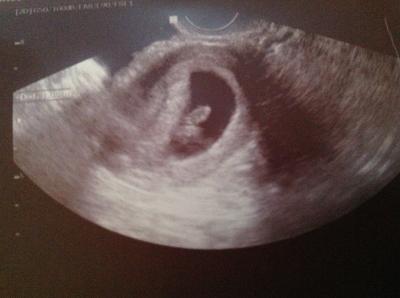

Hallo ihr lieben, mein Schatzi und ich waren ziemlich aufgeregt, auf Los ging's Los, meine Gyn sagte gleich: man hier ist ja was gewachsen, Herzchen schlug und die Knospen wo Arme und Beine wachsen sah man auch schon, aber irgendwie sah das komisch aus, ich fragte:das werden aber nicht zwei??? Meine Gyn: sie würde schon gucken, mein Schatzi: das ist doch prima, alles in einem Rutsch ... Ich dachte nur oh je oh je! Nach zwei Minuten die Erlösung, es war nur der Dottersack, puh! Nächster Termin ist am 09.01.13 zum großen Ultraschall, wo mein Schatzi gleich fragte die Ärztin ob er wieder mit kommen dürfte,süß! es ist schon unglaublich was so im Körper passiert, vor genau zwei Wochen war es so klein wie ein Reiskorn und heute 1,23 cm! Ein Bild ist anbei! Liebe Grüße

Bild zu Bericht vom Ultraschall - Forum für August - Mamis